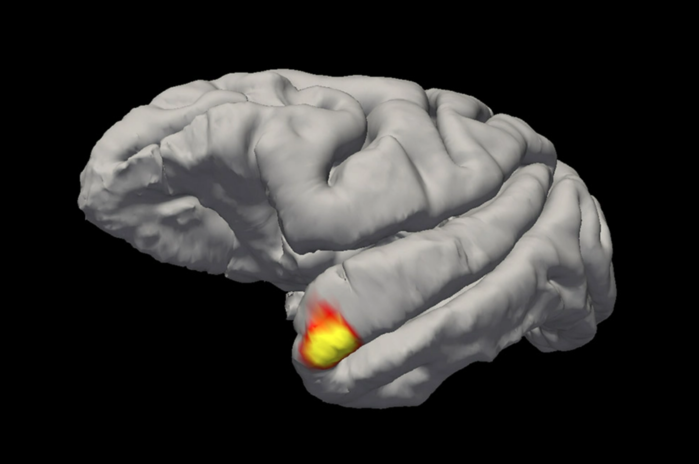

| ▲ "할머니 뉴런"은 측두엽의 정점에 위치한다. © Sofia Landi |

할머니-뉴런2021년 연구에서는 이를 더욱 정교하게 다듬었다. 이 연구에 따르면, 소위 "할머니 뉴런"은 안면 중추의 하위 영역인 측두극에 위치한다. 뉴욕 록펠러 대학교의 소피아 랜디(Sofia Landi)와 그녀의 팀은 "안면인식의 주요 모델들은 얼굴 인식을 처리하는 것부터 인식하는 것까지 순차적인 과정이 있다고 가정한다"고 설명했다. 그 이유는 얼굴 인식을 담당하는 영역이 먼저 우리의 기억과 연결되어야 하기 때문이다.

하지만 랜디와 그의 연구팀이 발견했듯이, 우리에게 매우 친숙한 얼굴, 즉 할머니, 부모님, 또는 친한 친구의 얼굴의 경우, 지름길이 있는 것으로 보인다. 측두극의 뉴런들은 기억을 먼저 참조하지 않고도 그러한 얼굴을 인식한다. 이 뉴런들은 특정 얼굴에 대한 기억을 저장해 두었다. 랜디는 "한편으로 이 세포들은 감각적이고 시각적이지만, 다른 한편으로는 기억 세포처럼 기능한다"고 설명했다. 흥미롭게도, 이러한 빠른 인식은 우리가 잘 알고 직접 만난 사람에게만 효과가 있다. 화면에서만 본 얼굴에는 효과가 없다.